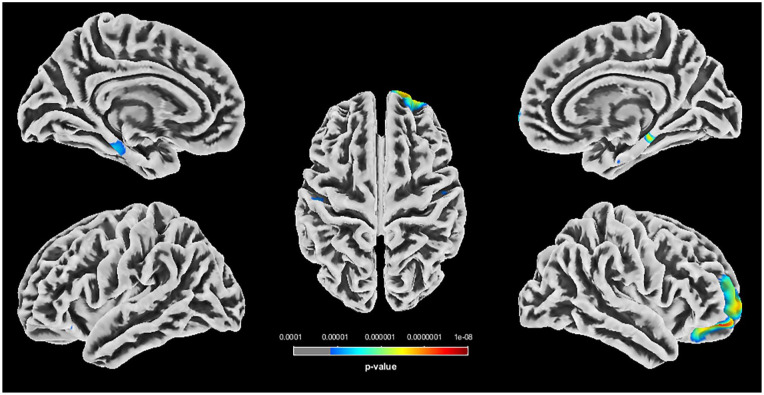

Results: We have found differences in grey matter volumes in the bilateral anterior hippocampus (left P < .001 and right P = .01) and left cerebellum exterior (Crus I) (P < .001). We have also found differences in cortical thickness in the bilateral parahippocampal gyri (left P = .001 and right P = .005) and right orbitofrontal cortex (OFC) (P < .001).